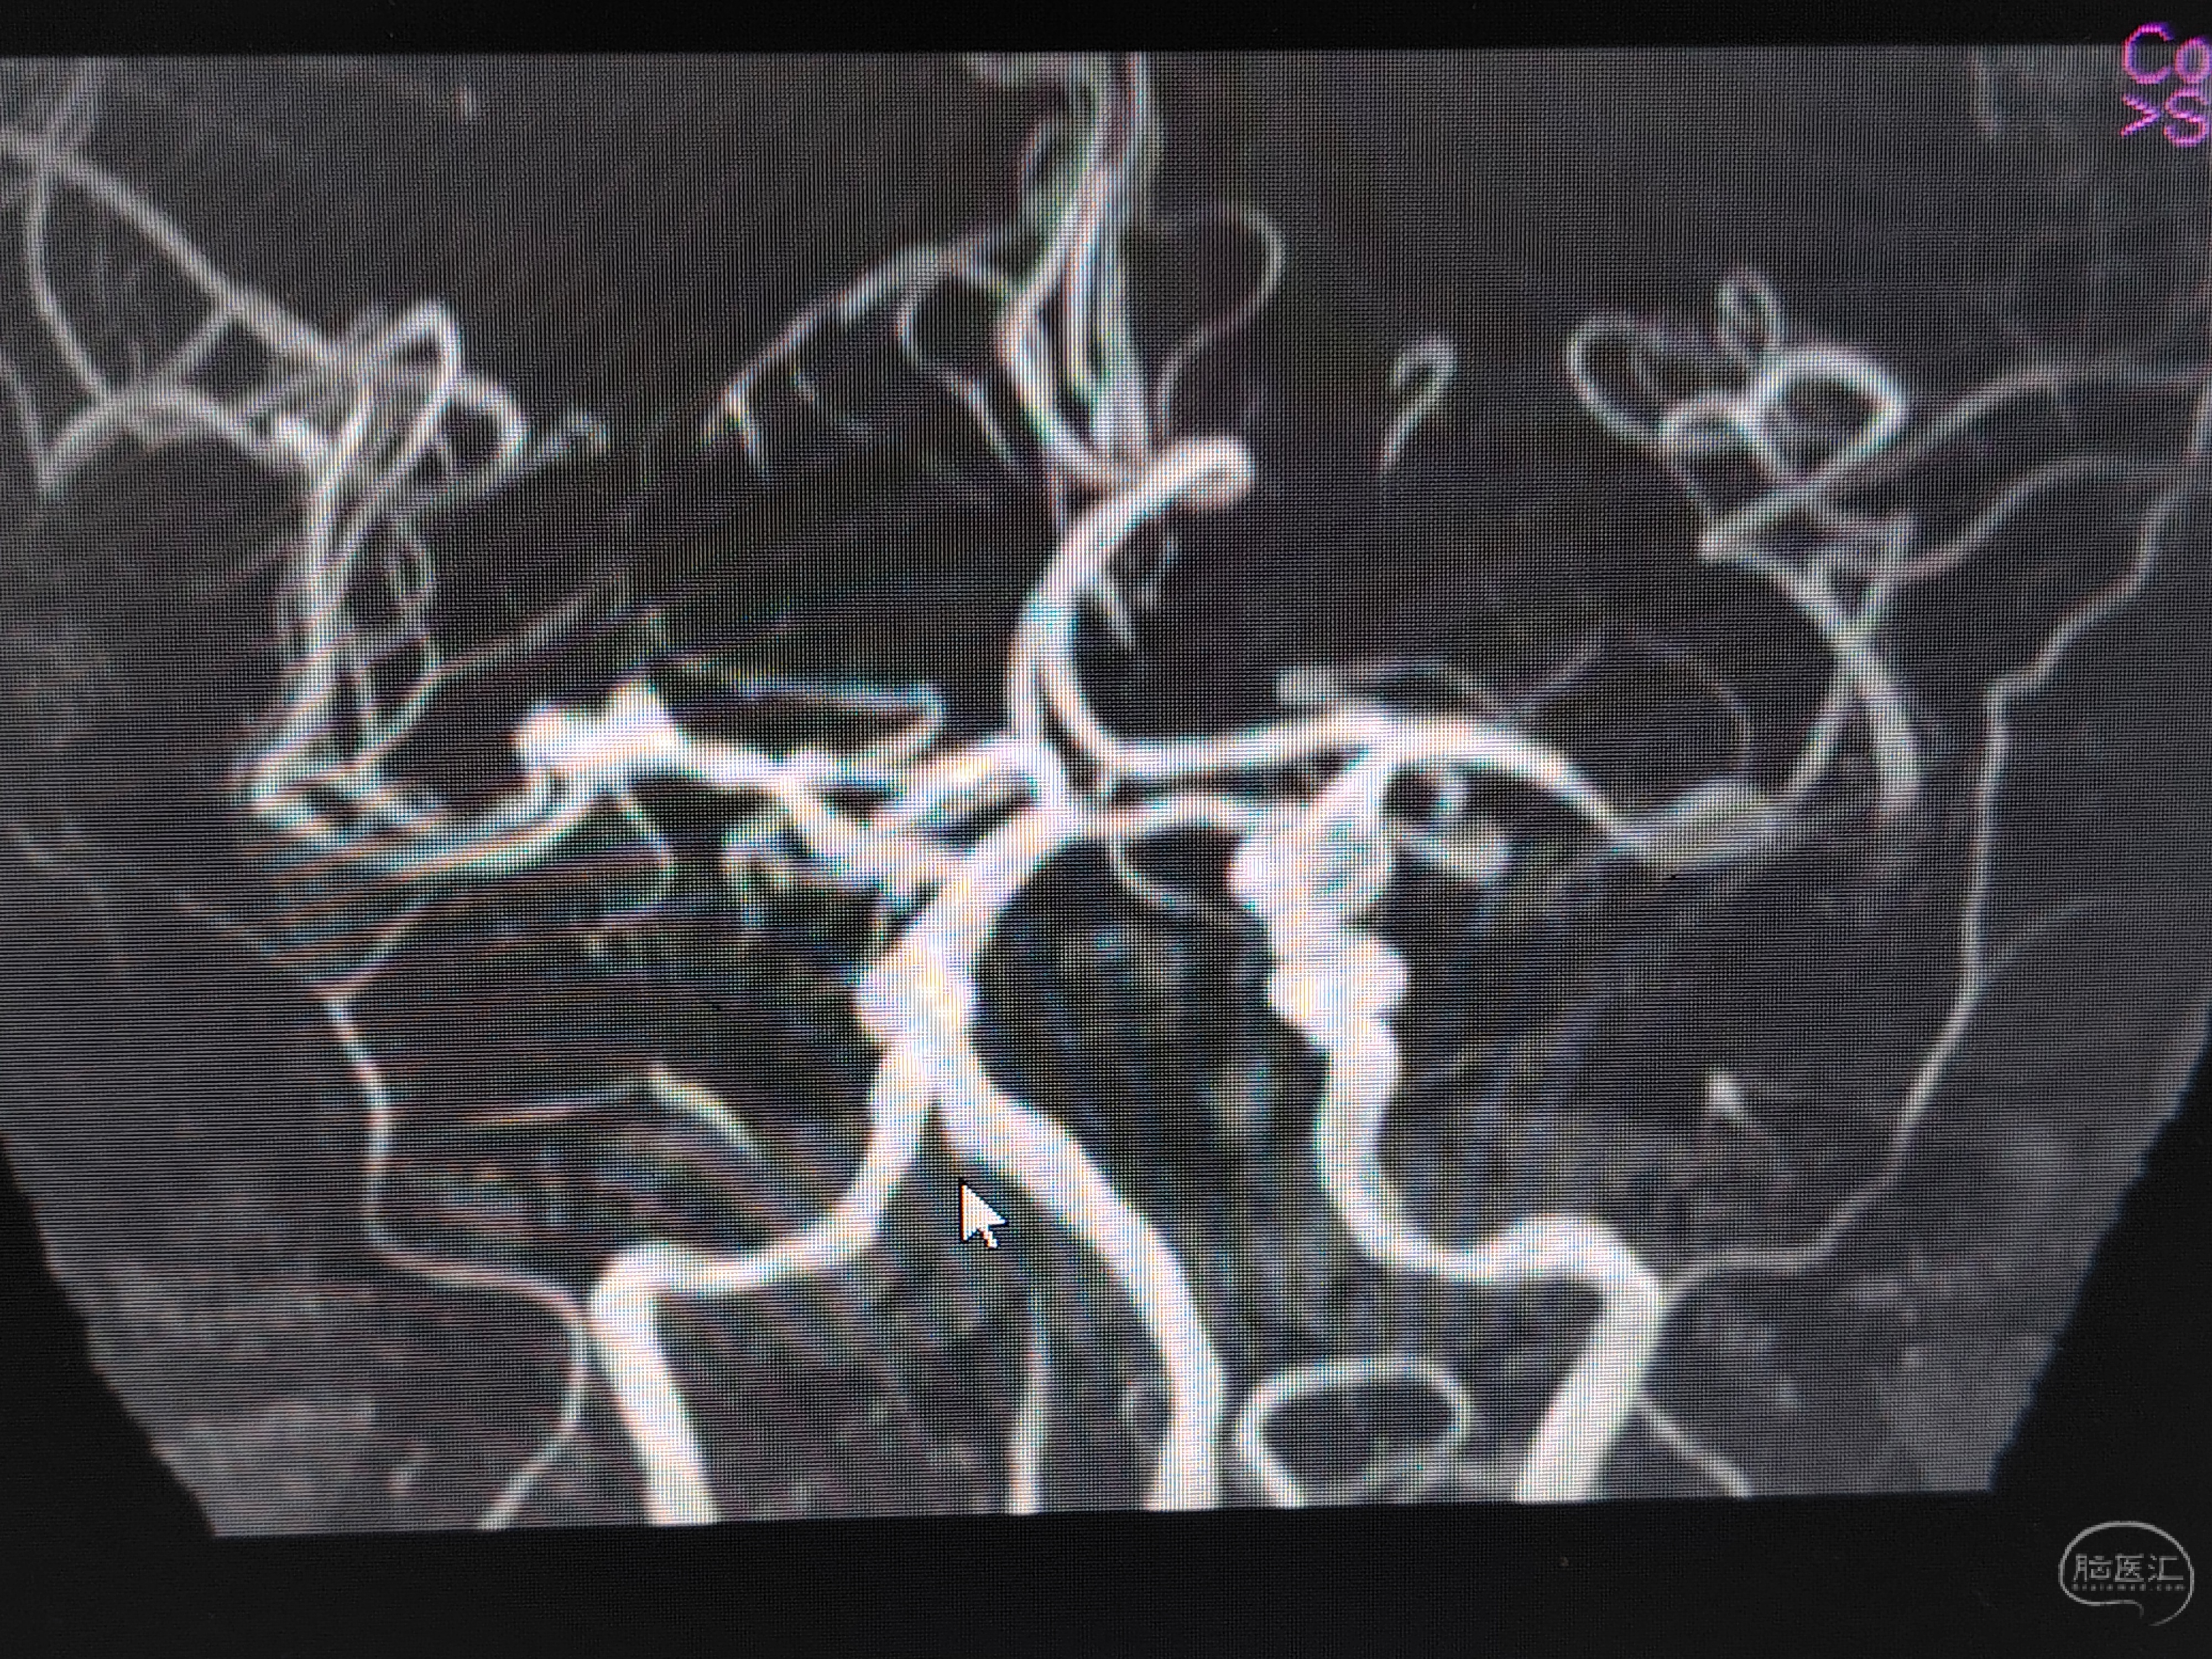

发病前MRA示颅内多发动脉瘤。

急症CTA颅内血管不显影。